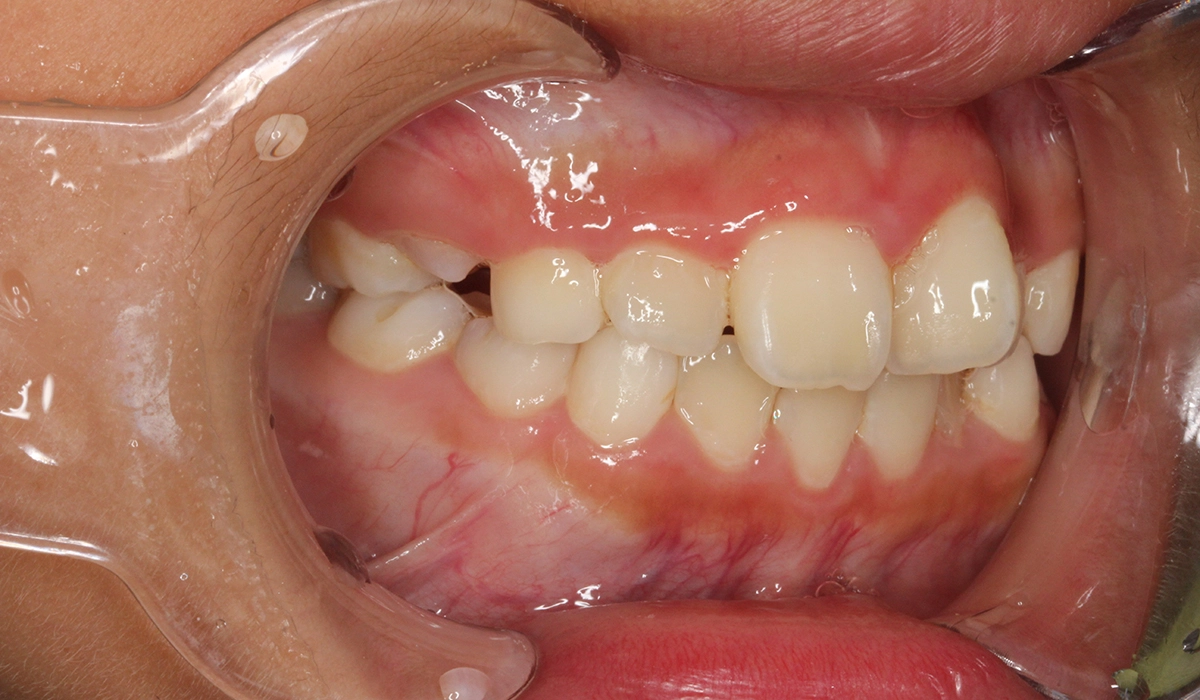

術前:左側